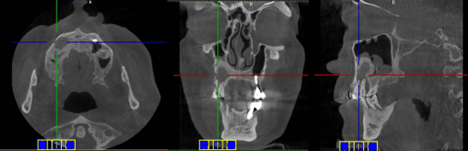

7、牙科常见的检查包括:CBCT(相比普通鼻窦CT能更好的显示牙齿问题,下图);口腔全景片,根尖X拍照,牙髓温度测试

根尖周炎:冷热试验; CBCT、口腔全景片PAR 或 根尖拍片OP

1)鼻窦CT发现上颌窦浑浊,尤其单侧,需留意上列牙齿问题。常规的鼻窦CT现实不足的部分,需要进一步的专科检查以排除牙源问题。